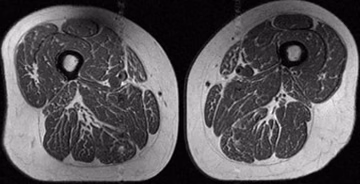

Ultra predelana živila spreminjajo človeška stegna v "dobro marmorirane zrezke" Zdravje | pred 4 min. | 0